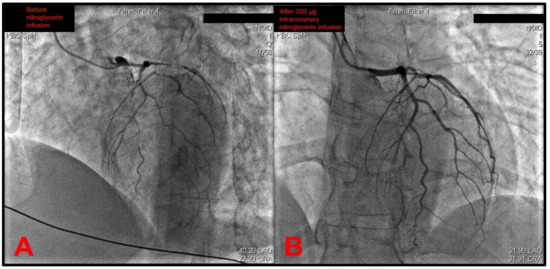

The catheter was then exchanged, and the left coronary artery (LCA) was later intubated. This revealed a gracile left coronary circulation characterized by the narrow-caliber LM that was prone to spasm and a narrow caliber LAD that featured a slow flow as well as the angiographical picture of an intramural hematoma due to a spontaneous coronary artery dissection (SCAD) originating from the left main stem (Figure 2A). A differential diagnosis of severe diffuse coronary vasospasm was considered as well, given the narrow and gracile caliber of all vessels originating from the left main stem. The circumflex artery (Cx) was found to have a slow flow, and it also featured severe diffuse spasms. Furthermore, it also gave off a strong marginal branch that had slow flow and had a significantly larger diameter than the circumflex. The intermediate branch was also observed to be characterized by gracile morphology, slow flow, and subocclusion of the proximal segment. An intracoronary infusion of 200 μg of nitroglycerin significantly recovered the distal flow through the left coronary tree (Figure 2B). Although it would be an appropriate step to perform intracoronary imaging to confirm the suspected SCAD diagnosis, this was not performed due to a lack of dedicated devices in the cath lab at the time.

Figure 2. (A) An emergent coronary angiography revealed no atherothrombotic occlusions and a gracile aspect of the whole left coronary tree with most probable differential diagnoses of severe diffuse coronary vasospasm or extensive intramural hematoma due to a spontaneous coronary artery dissection (SCAD)—in this case originating from the left main stem. (B) Distal coronary flow significantly improved after an intracoronary infusion of 200 micrograms of nitroglycerin. Note: operator name, patient information, and procedure date have been de-identified from the original images.